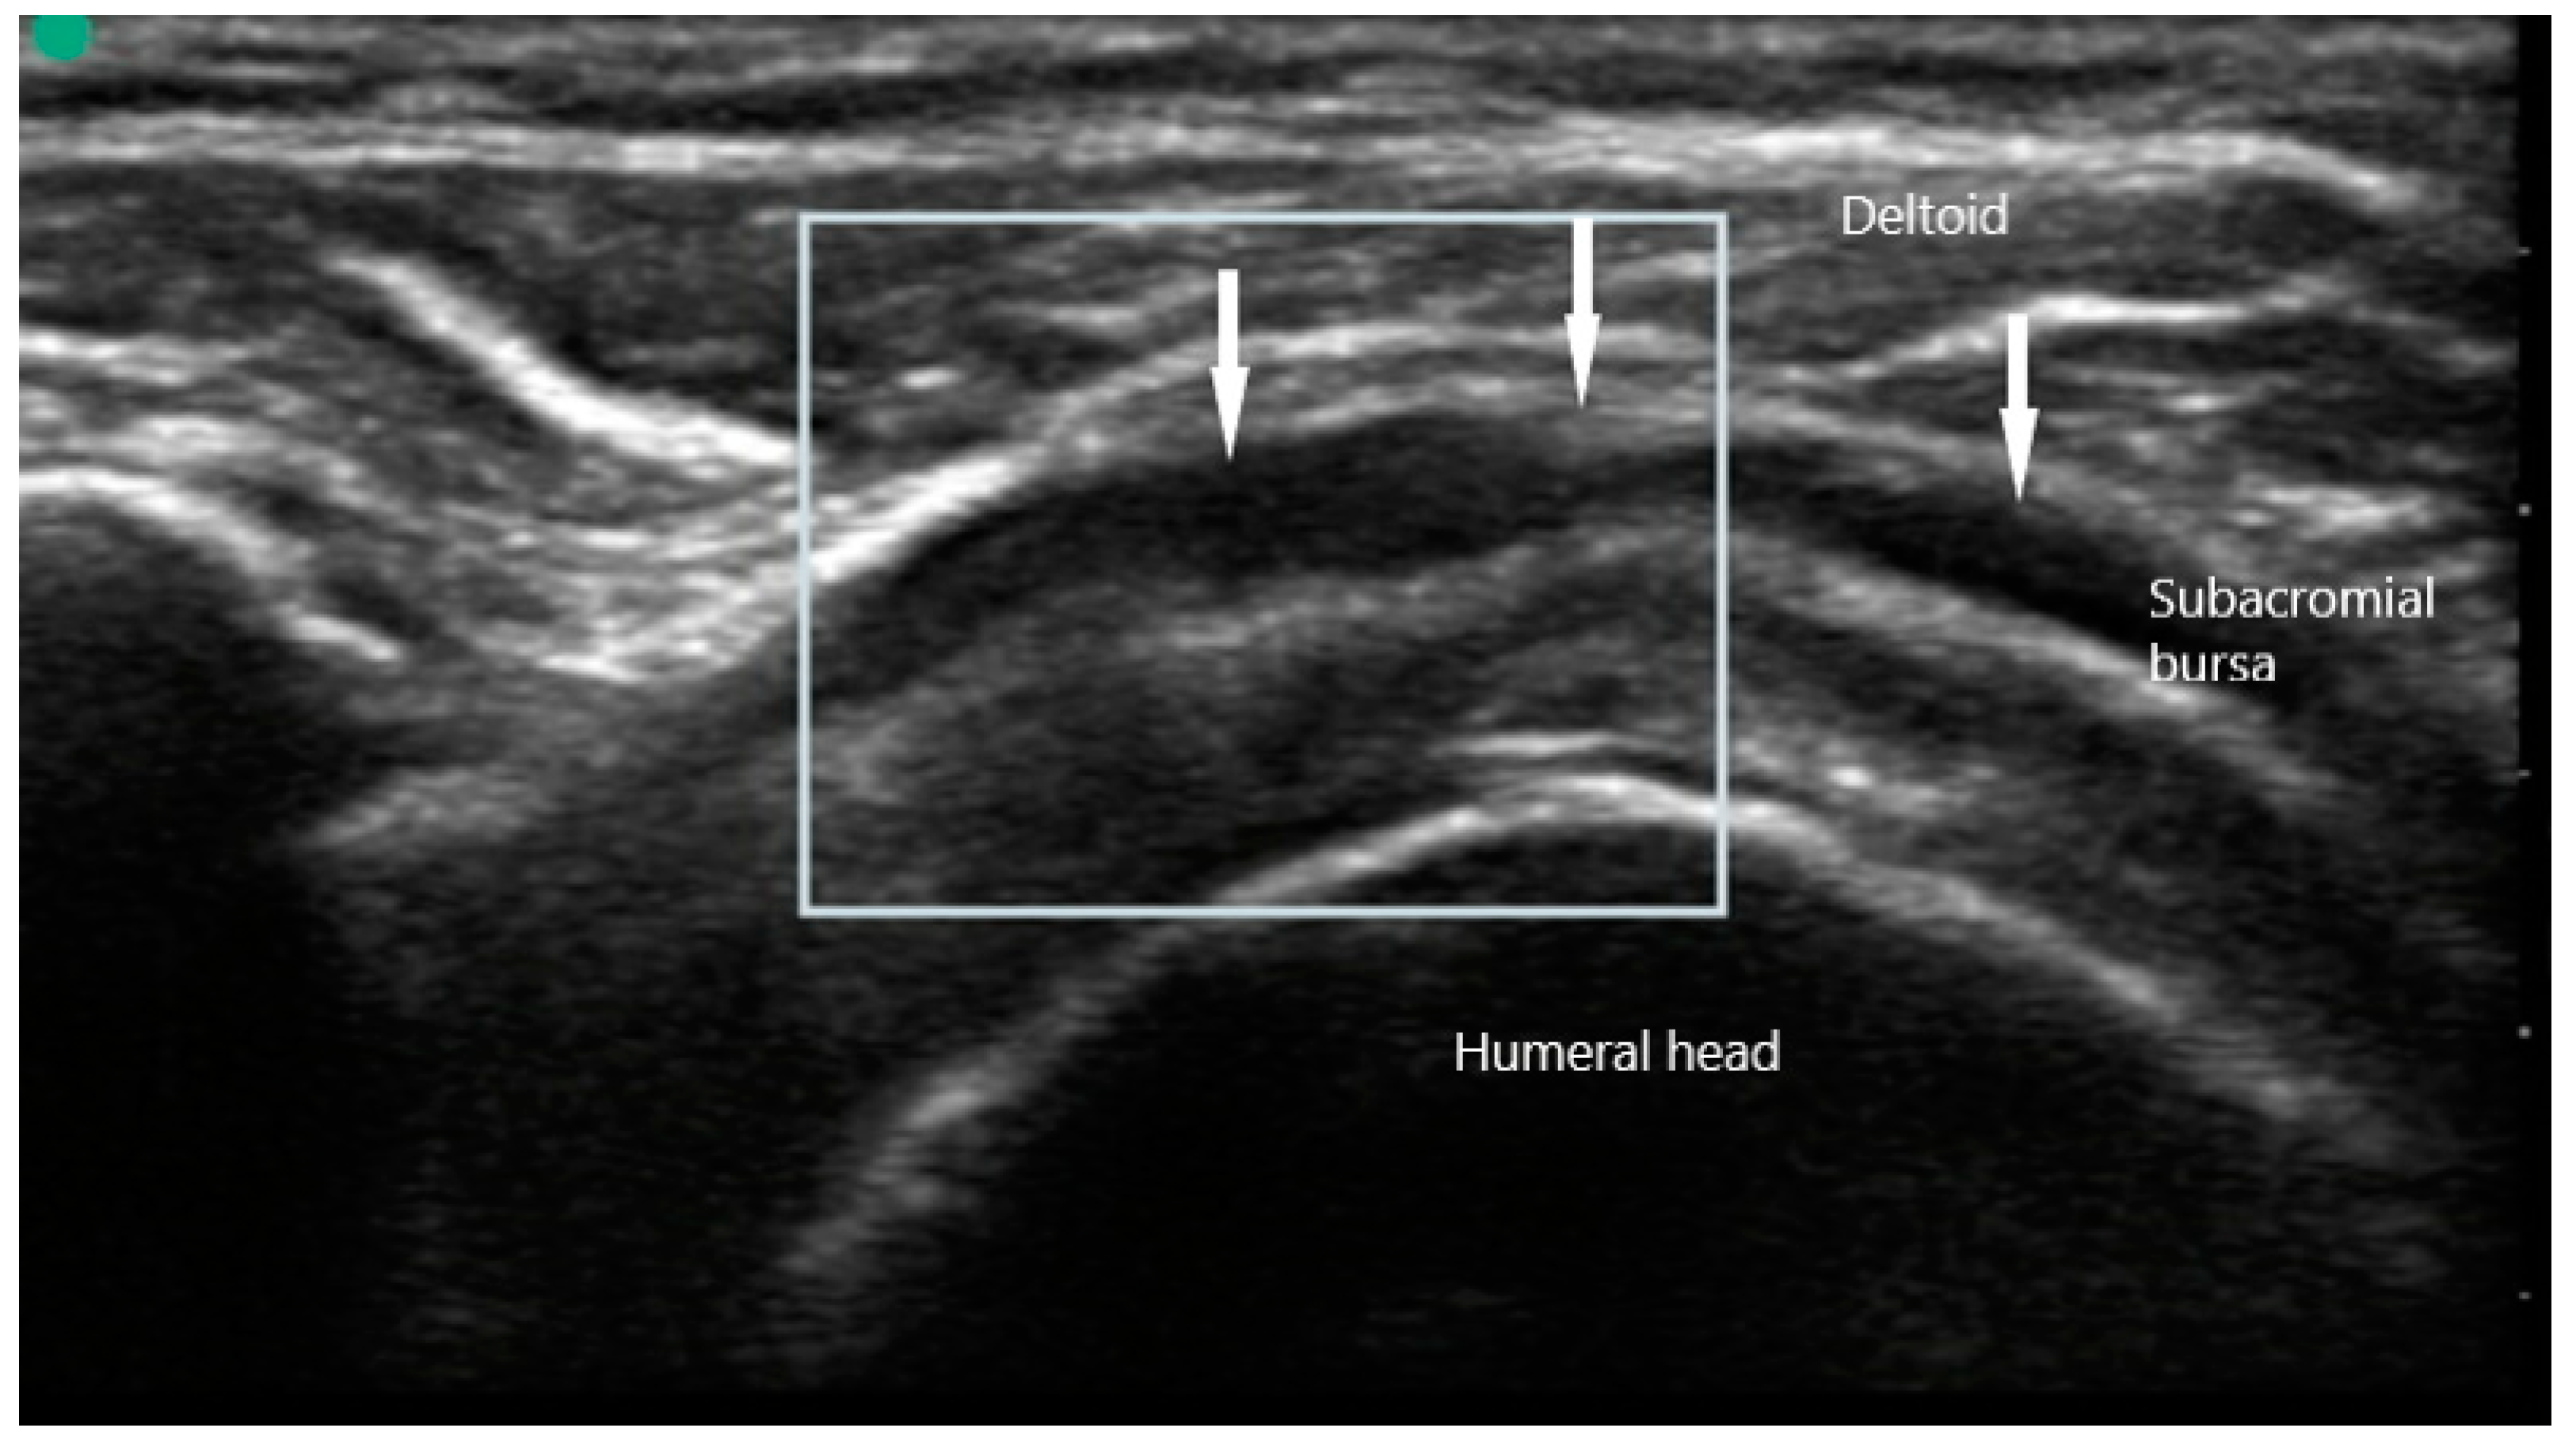

US findings in patient with PMR frequently reveal inflammatory changes of the affected joints, along with peri-articular structures. Shoulder pain may manifest on MSUS as subacromial bursitis (Figure 8) and is seen as a hypoechoic collection superficial to the supraspinatus. Other findings may include bicipital tenosynovitis and glenohumeral effusion. Pain of the hip girdle commonly reveals hip effusion and trochanteric bursitis. These findings are non-specific, but may offer crucial evidence when taking into the context the wider clinical picture. While all these US findings may be present due to mechanical etiologies, bilateral involvement as well as severity of the inflammation can suggest an inflammatory component.

Figure 8. Subacromial bursitis (arrows) overlying supraspinatus in polymyalgia rheumatica.